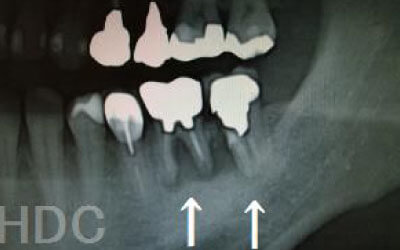

お口の状態や噛み合わせによって異なるため一概には言えませんが、一般的には奥歯、特に大臼歯と言われる一番奥とその隣の二番目の歯の部分がお勧めです。

この2本の奥歯は、噛み合わせの力の60%以上を支えているため、ここをインプラントでしっかり治療することが望ましいです。